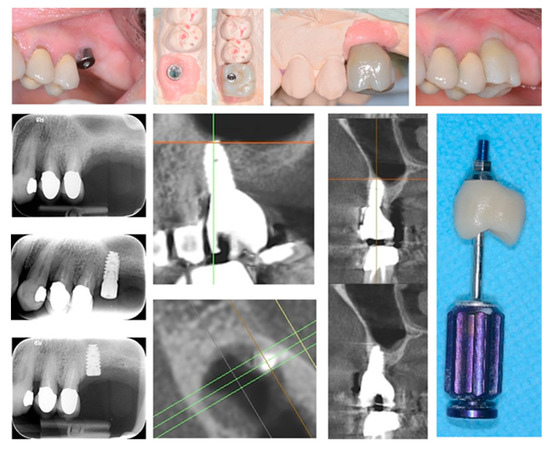

In all cases, fixtures were placed with high insertion torque (up to 50 Ncm) and with atraumatic crestal lifting of the sinus membrane (Figure 2a–c and Figure 3a–f). Prostheses were placed 3 months after surgery; more precisely, 40 were cemented metal–ceramic crowns, and the remaining were screwed hybrid ceramic crowns (Vita Enamic Multicolor) with glued titanium bases (Figure 4). All implants had a diameter of 4.2 mm, and 35 were 6.25 mm in length, while the remaining 45 had a length of 8 mm (Figure 5).

Figure 3. Single tooth restoration by screw-retained crown digitally planned by computer aided design (CAD) and CBCT (a); implant insertion was assisted by a surgical guide (be); fixture position was pre-operatively planned by simulation of crestal sinus membrane elevation (f,g).

Figure 4. Implant-supported single tooth restoration in atrophic posterior maxilla with all of the pre- and post-surgical phases until final screw-retained prosthetic rehabilitation.